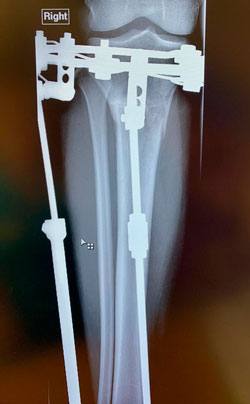

Рентген перед снятием аппаратов 85 дней

правая прямая проекция